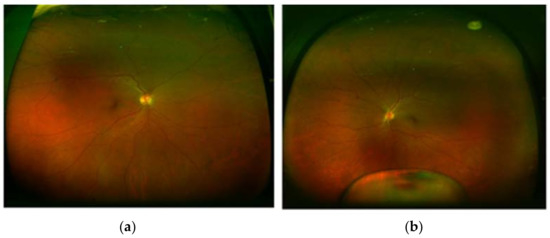

2. Case Presentation